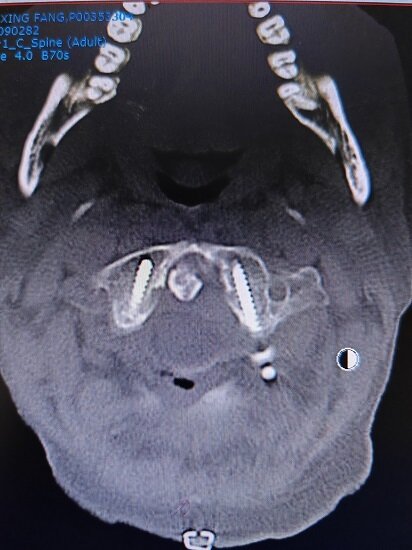

但在经过CT扫描等常规检查过后,孟凡志发现棘手所在,患者病情并非单纯的关节炎病引起,亟需手术治疗——医学影像显示,该患者入院时已罹患寰枢椎脱位,病情凶险。“一个喷嚏或者睡梦中的一次翻身可能就会导致高位颈髓损伤、心脏骤停。”孟凡志如是说。

“寰枢椎脱位,是指是人体第一颈椎(寰椎)和第二颈椎(枢椎)之间失去正常的关节对位。”孟凡志介绍,除了影响颈椎旋转功能,寰枢椎脱位最大的危害是导致高位颈脊髓受压,严重时可导致瘫痪。“目前治疗方案主要采取颈椎后路减压植骨融合手术,稳定重建之后炎症反应可有不同程度减轻,颈椎疼痛也可以得到明显改善。”

由于患者年龄较大,本身手术存在一定风险性。基于此,孟凡志与医疗团队针对患者手术方案的可行性进行了细致讨论。“我们通过充分模拟手术情况,并应用CT血管成像技术,提供准确与真实的术前组织解剖资料,分辨出椎弓根及椎动脉位置关系,这大大提高了手术的安全性。”孟凡志回忆。

“高位颈椎手术存在一定的风险和挑战,而类风湿性关节炎造成颈椎正常解剖结构的消失更是增加了手术难度。”孟凡志介绍。最终,团队为患者确定了“颈后路寰枢椎脱位复位术+钉棒系统内固定+后外侧植融合术”的手术方案。以通过将寰枢椎复位固定,达到恢复颈椎稳定性的效果。

(手术前)

(手术后)